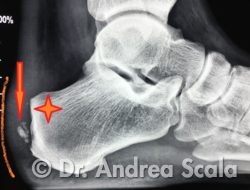

La semplice Radiografia evidenzia immediatamente i dati clinici salienti: la sporgenza ossea, l’ispessimento e il gonfiore dei “tessuti molli”, l’irregolarità della inserzione del tendine d’achille sul calcagno.